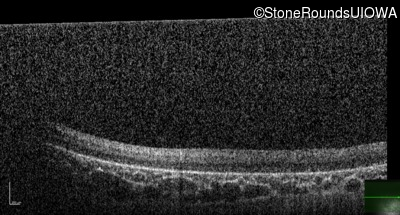

Optical Coherence Tomography - Right - No Light Perception

Exemplar / OCT Stack